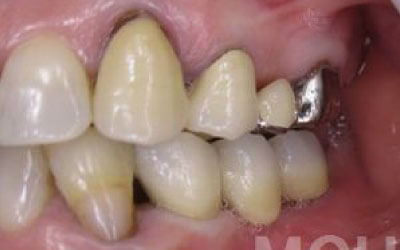

一方、インプラントは人工の歯根が顎の骨に直接固定されるため、残っている歯にかかる負担を大幅に軽減できます。

一方でインプラント治療なら、周囲の歯を削ったり神経を抜いたりする必要がないため、健康な歯を守りながら歯の寿命を延ばすことができます。

インプラントの利点は、入れ歯のように取り外す必要がなく、ご自身の歯のように自然に噛める点です。

そして最大の利点は、周囲の歯の寿命を短くしないことです。

ブリッジや入れ歯では、他の歯に負担がかかり、歯が連鎖的に抜けていくことがあります。

しかし、インプラントは周囲の歯に一切負担をかけないため、残った歯にとって最も優しい治療法です。